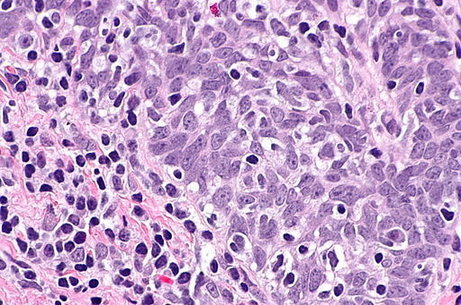

The research by Nathan Benaich [2010] is based on his PhD in Oncology, following an MPhil in Biological Science [Genetics]. It focuses on head and neck squamous cell carcinoma (HNSCC) which receives little attention in the cancer research community despite its increasing incidence and a stagnant five-year survival rate of approximately 50%. In fact, HNSCC is the sixth most common form of cancer worldwide.

*Picture of squamous cell carcinoma courtesy of Wiki Commons.